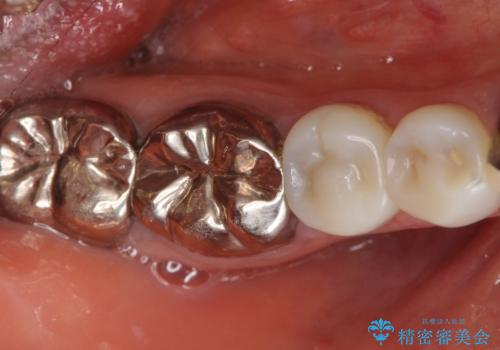

精査したところ、被せ物を入れたばかりの右下の小臼歯(右下5)は不可逆性歯髄炎により神経をとる処置(抜髄)が必要な状態でした。

根管治療後、セラミッククラウンによる補綴治療を行いました。

クラウンの種類:オールセラミッククラウン エコノミー